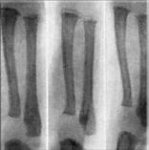

Рахит у детей: симптомы и лечение Дети сейчас болеют на много чаще и больше чем взрослые ведь с каждым годом экология стает все хуже и хуже, а иммунитет у детей слабеет из-за плохого образа жизни их родителей. Многие мамы пьют во время беременности, курят практически каждый день и вообще ведут себя неподобающим образом. Это сказывается на ребенке, который из-за определенных недостатков в витаминах может получить болезнь, которую вылечить просто нельзя. Рахит у детей это самая распространенная болезнь, которую вылечит пока никто не смог. Появляется она по самым разным причинам, но девяносто процентов причины это недостаток витамина D в организме новорожденного. Опять же приводит к такому недостатку плохое питание и вредные привычки мамы и папы, которые не думаю о здоровье ребенка. Есть конечно и другие причины возникновения болезни, но они очень редко встречаются.Лечить рахит можно, но толку от этого, к сожалению, вообще нету. Ни одни таблетки не помогут костям правильно развиваться и уж тем более нарушенной ориентации в пространстве таблетками и уколами тоже не поможешь. Остается только помогать ребенку физически и морально. Физическая помощь иногда бывает даже лишней ребенок растет и привыкает жить с теми возможностями, которые у него есть, а вот на моральном уровне помощь от родителей, конечно, необходима. Найти школу для ребенка, научить его не обращать внимания на окружающих это все задача родителей, от которых зависит как будет ощущать себя ребенок в обществе. И хотя многие говорят, что такие дети не могут работать и учится статистика показывает, что многие дети с болезнью рахита стают очень умными и профессиональными людьми у них больше времени на изучение чего-то, ведь гулять и отвлекаться в силу своей болезни у них не получится. Так что главное в нашей жизни на все смотреть позитивно. |

Дети сейчас болеют на много чаще и больше чем взрослые ведь с каждым годом экология стает все хуже и хуже, а иммунитет у детей слабеет из-за плохого образа жизни их родителей. Многие мамы пьют во время беременности, курят практически каждый день и вообще ведут себя неподобающим образом. Это сказывается на ребенке, который из-за определенных недостатков в витаминах может получить болезнь, которую вылечить просто нельзя. Рахит у детей это самая распространенная болезнь, которую вылечит пока никто не смог. Появляется она по самым разным причинам, но девяносто процентов причины это недостаток витамина D в организме новорожденного. Опять же приводит к такому недостатку плохое питание и вредные привычки мамы и папы, которые не думаю о здоровье ребенка. Есть конечно и другие причины возникновения болезни, но они очень редко встречаются.